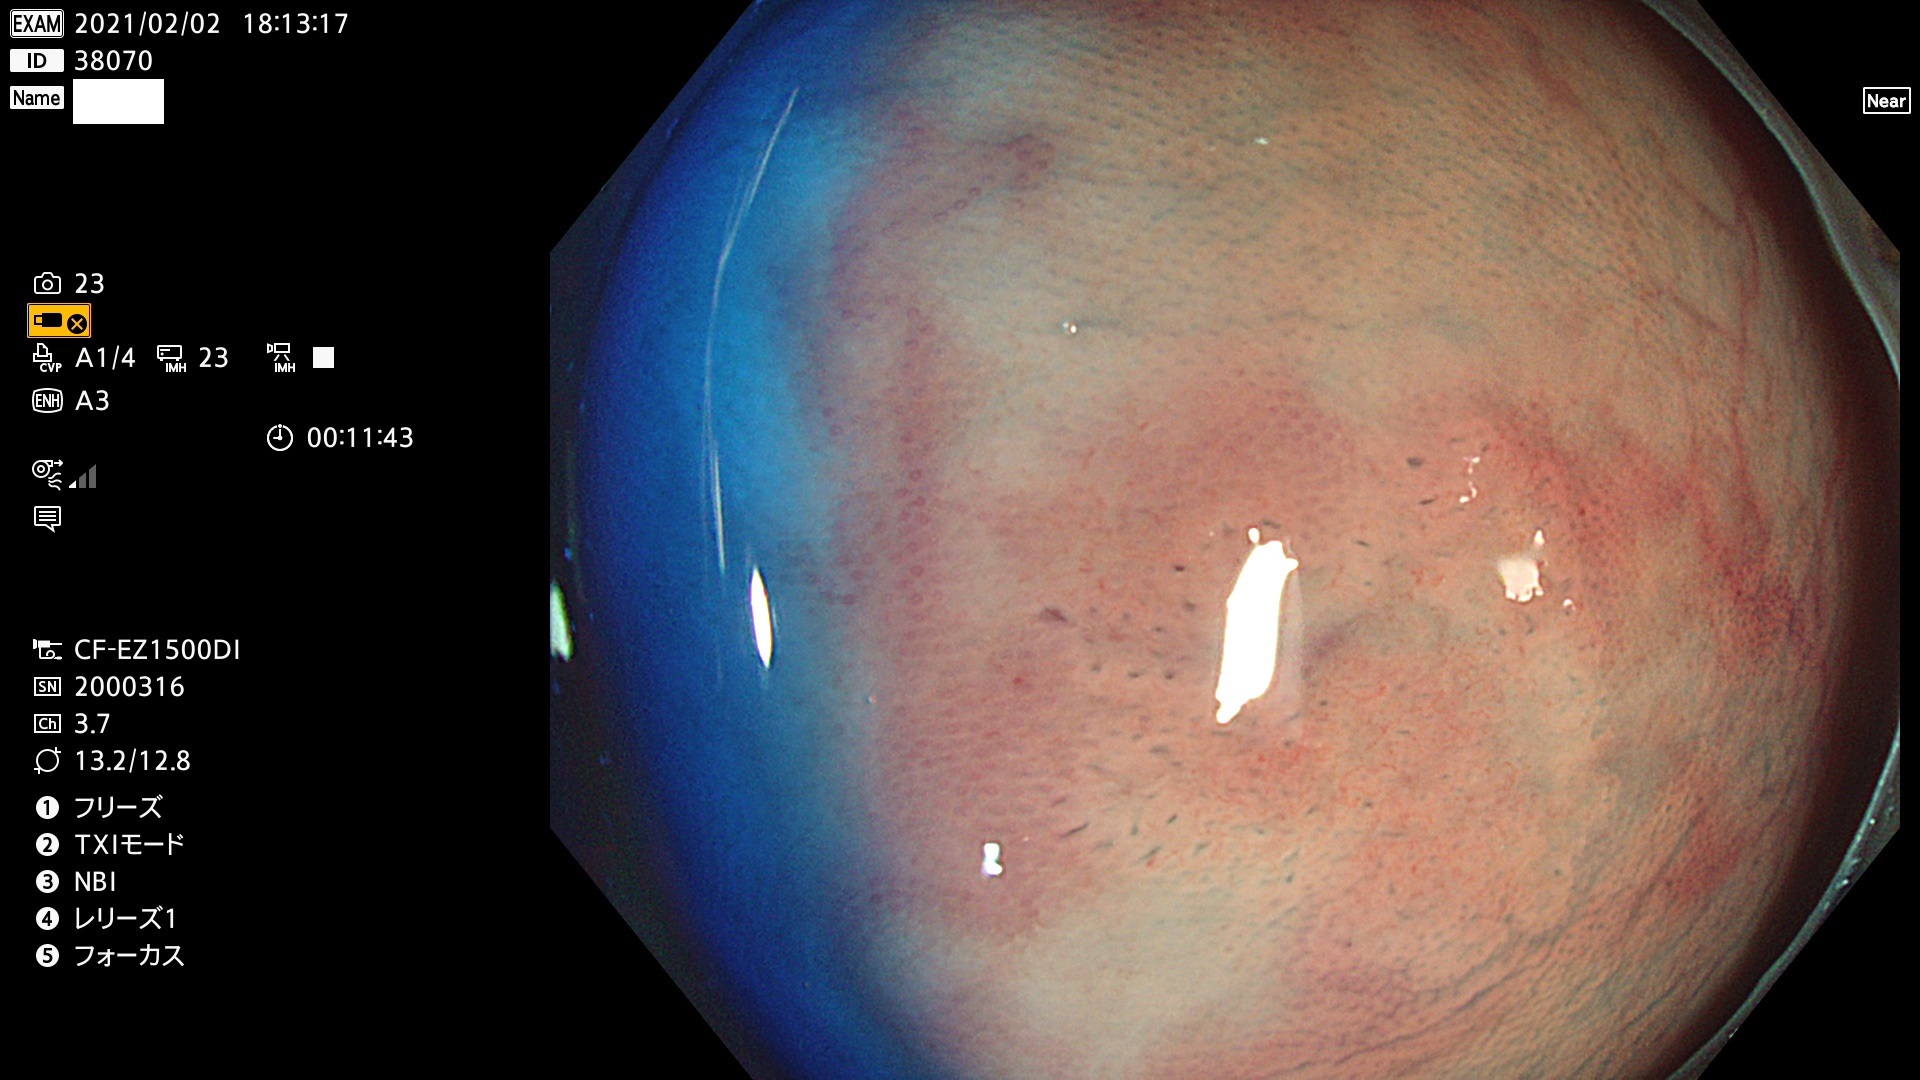

38001 38002 38003 38004 38006(SSAPのみ) 38007 38008 38009 38010 38012 38013 38014 38016 38018 38020 38021 38025 38026 38029 38032 38033 38034 38035 38036 38037(SSAPのみ) 38039 38043 38044 38048 38049 38050 38052 38055 38056 38057 38058 38059 38064(SSAPのみ) 38065 38068 38069 38070 38071 38072 38074 38075 38076 38078 38079 38080 38082 38083 38084 38085(SSAPのみ) 38086 38087 38088 38089 38090 38091 38092 38093 38094 38097 38098 38099

発見困難で危険性の高い平坦型病変(上記100名より抽出)